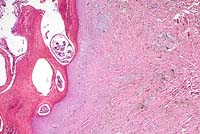

Case 9-4. Skin. Knemidocoptes mutans mites in burrows within a thickened, anuclear keratin layer. Some slender dendritic melanin-laden cells are in the deep dermis (right). 10X

AFIP Diagnosis: Skin, non-feathered: Dermatitis, lymphohistiocytic, superficial and perivascular, chronic, diffuse, moderate, with epithelial hyperplasia, severe orthokeratotic hyperkeratosis, and intracorneal arthropods, Chinese silky chicken, avian.

Contributor's Diagnosis and Comments: Marked hyperplastic superficial perivascular dermatitis with intra-corneal arthropod parasites (Knemidocoptes mutans).

At necropsy, the most striking finding is that of the diffuse black pigmentation of skin and other tissues. On histological evaluation, numerous melanin containing melanocytes are present, which are a normal finding in the tissues of these birds. Chinese Silky chickens are desired by some members of the oriental community for medicinal purposes. They are also raised for consumption. Although the cost of production is high and the birds grow slowly, itis felt that the enterprise can still be profitable since the market is so specialized.